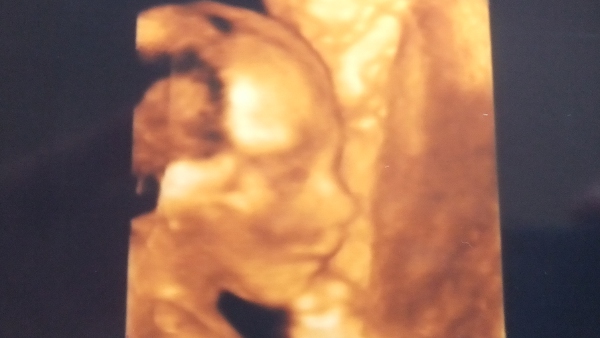

No, nem kéretem magam tovább, íme a babák :)

Kép Miksa 26+3

Kép Stefánia 19+3

Stefi már nem mutogatja magát (ez a19 hetes fotó is hosszas unszolásra készült a genetikai uh-n)

Oroszagár, csodálatosanszépségesengyönyörűek a bébikék :lol: Olyan hihetetlenek ezek a felvételek...

De gyönyörűek! Hihetetlen, hogy már ismerheted őket, a mozdulataikat, mielőtt a kezedbe vennéd őket! Csodálatos, nem?

Köszi lányok, tényleg csoda ez az ultrahang. Mennyi minden törént mióta megszülettünk! Akkor még nem volt uh (legalábbis itt nem csináltak), az első lombikbaba is utánam született :D Nagyon jó nézegetni őket, és most már hason keresztül is lehet velük játszani, nagyon vicces, ahogy átrendezik a hasam formáját néha :D De ezt ti is mind meg fogjátok tapasztalni :!: